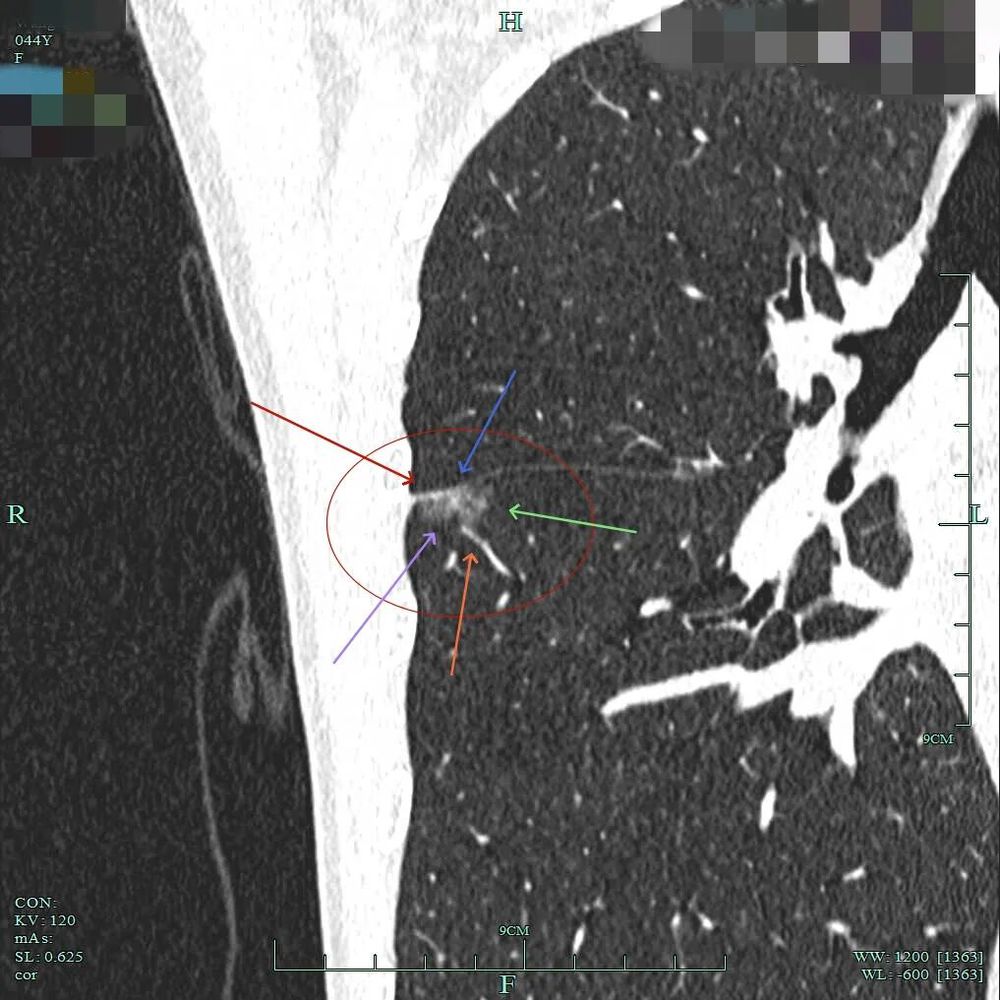

小血管进入以及灶内小部分密度偏高,与叶间裂没有间隙,是紧贴的。

灶内密度不均,叶间裂处增厚与密度增高,血管进入,表面不平以及细毛刺可见。

病灶混合密度,实性成分有收缩力与纠集感,磨玻璃部分密度较低,表面不平,细毛刺可见,紧贴叶间裂。